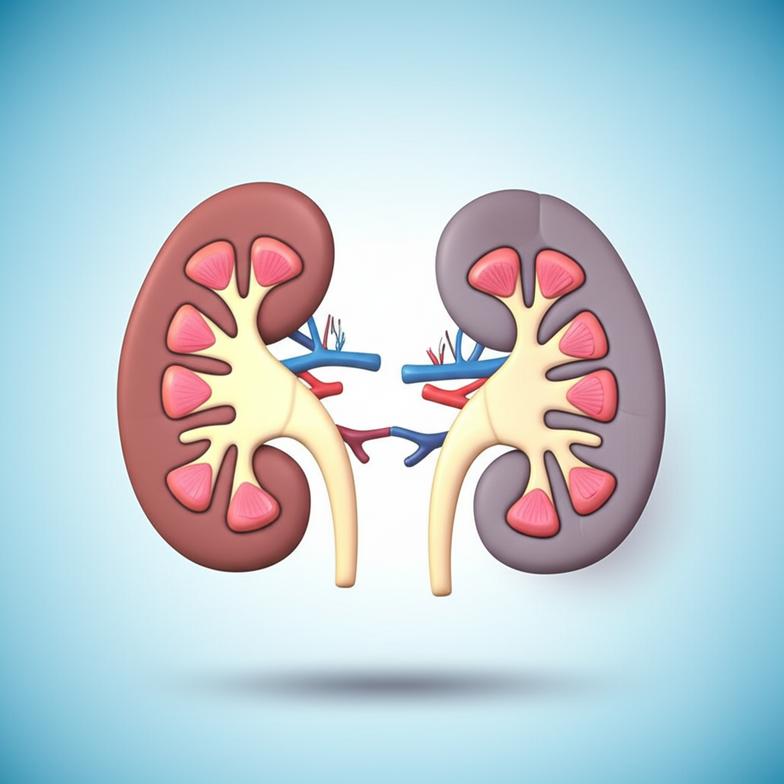

กลไกการทำงานของไตและการเสื่อมสภาพตามวัย

ไตเป็นอวัยวะคู่ที่มีความสำคัญอย่างยิ่งในการดำรงชีวิต มีหน้าที่หลักในการกรองของเสีย สารพิษ และน้ำส่วนเกินออกจากเลือด เพื่อรักษาสมดุลของน้ำ เกลือแร่ และความเป็นกรด-ด่างในร่างกาย นอกจากนี้ ไตยังมีบทบาทในการผลิตฮอร์โมนที่ควบคุมความดันโลหิต กระตุ้นการสร้างเม็ดเลือดแดง และช่วยในการกระตุ้นวิตามินดีให้ทำงาน ภาวะไตเสื่อมหรือโรคไตเรื้อรังมักเป็นกระบวนการที่ดำเนินไปอย่างช้าๆ โดยที่ผู้ป่วยอาจไม่แสดงอาการใดๆ ในระยะแรกเริ่ม จนกระทั่งการทำงานของไตลดลงอย่างมาก จึงจะเริ่มมีอาการปรากฏ